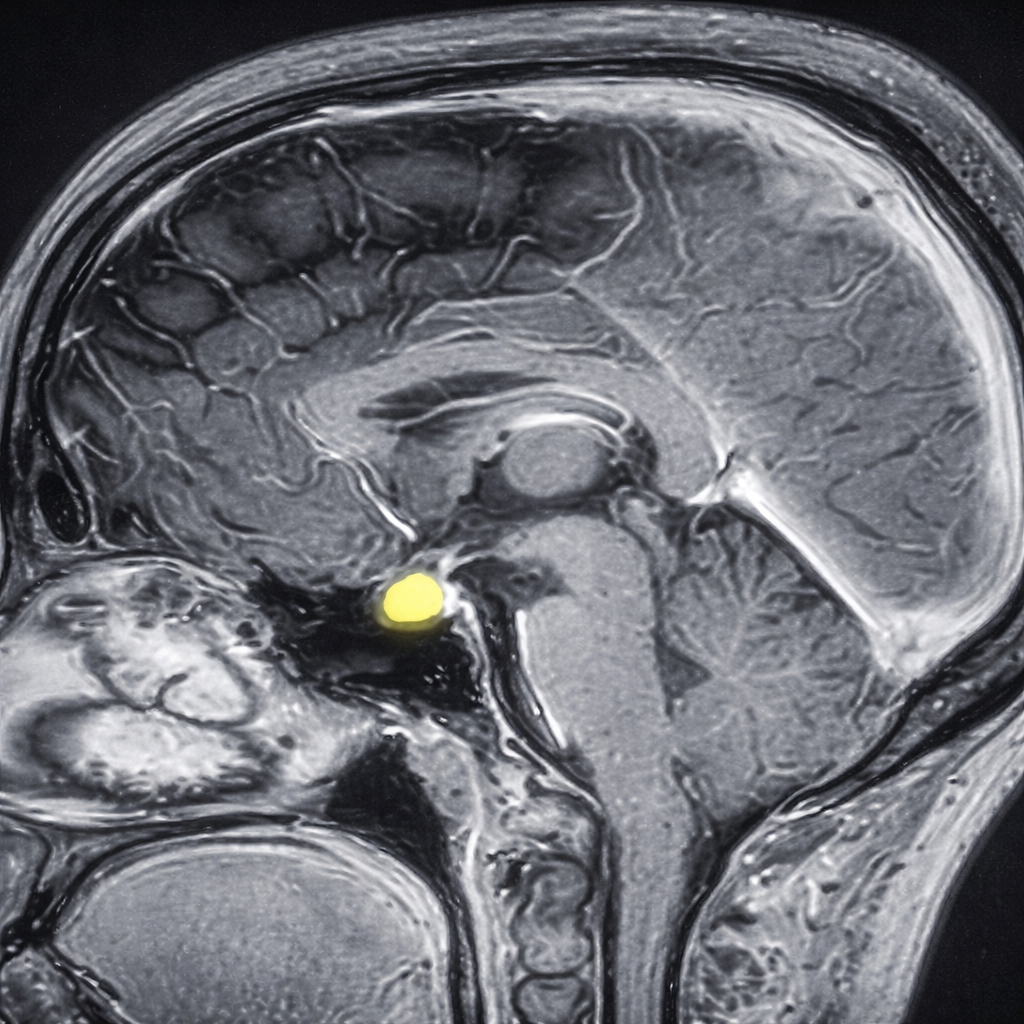

Quistes en la bolsa de Rathke

• Resonancia magnética (MRI), la cual permite visualizar el quiste y su relación con estructuras cercanas.